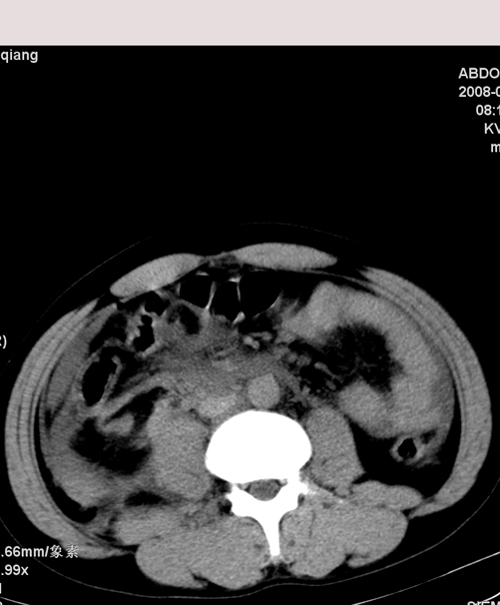

以下是引用muzi888在2008-7-15 10:45:00的发言:[br]大量腹腔积液,气腹,肾皮质弧形高密度影,诊断;1 空腔脏器穿孔 2 右肾包膜下血肿

以下是引用随光逐影在2008-7-15 11:18:00的发言:[br]考虑为:1)腹部空腔脏器穿孔。2)右肾破裂并肾包膜下血肿,肾盂积血。3)腹水(血)。